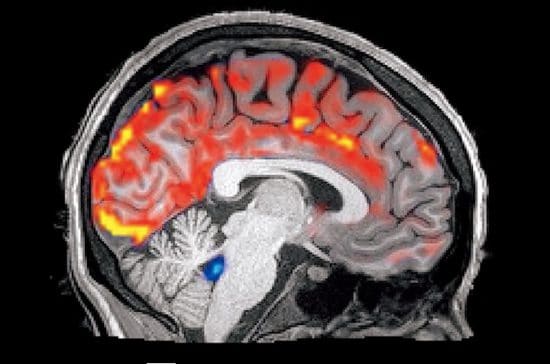

「ハーバード大学の最新の研究によれば、20代の学生がたった一晩徹夜しただけでアミロイドβが2~3%増えていた。一見、些細なことで20~30年後の認知症リスクが高まるのだから怖い話です」

だが、やみくもに長時間の睡眠を取ったからといって、不足した睡眠を取り返せるわけではない。白澤氏が続ける。「寝だめで寝不足は解消できません。睡眠は“貯蓄”できないのです。恒常的に長時間の睡眠を取っても、睡眠の質が悪ければ脳のゴミは溜まっていくばかり。睡眠時間だけで睡眠の質は測れません」

「良質な睡眠を十分に取れば、一日分の脳のゴミは洗い流せるでしょう。ただ、ゴミは毎日溜まるので、一日だけでは意味がない。ボーッとしたりするのは、その人に必要な睡眠時間に足りていないから。一日単位では問題なくとも、1週間、1か月単位でのしわ寄せが“睡眠負債”となって積み上がっていく。これを解消するには1~2か月要するので、一日や2日の寝だめでは効果が望めません」